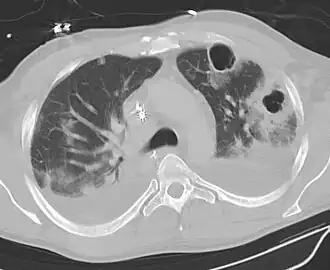

Les abcès pulmonaires sont souvent d'un seul côté et concernent les segments postérieurs des lobes supérieurs et les segments apicaux des lobes inférieurs, car ces zones dépendent de la gravité en position couchée. La présence de niveaux air-fluide implique une rupture dans l'arbre bronchique ou, rarement, la croissance d'un organisme gazogène.[réf. nécessaire]

Un abcès sous-pleural.